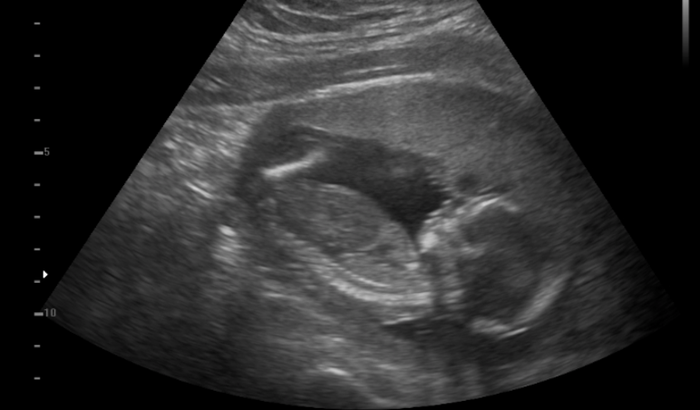

Eu tenho 27 anos estou grávida de 4 meses essa é a minha quarta gestação as minhas três últimas gestações eu perdi os bebês nunca consegui levar a gravidez adiante, eu quero muito conseguir levar essa, MINHA GRAVIDEZ É DE ALTO RISCO.

Uma amiga me deu a ideia de fazer uma vaquinha online, para conseguir fazer o tratamento no particular e o parto também, com ajuda de alguns amigos consegui arrecadar um valor e começar o tratamento no particular tive uma consulta com uma médica maravilhosa doutora Rochelle Hygino que na primeira consulta já me encaminhou para internação e para cirurgia, precisei fazer uma cerclagem no útero que é costurar o útero para segurar o bebê.